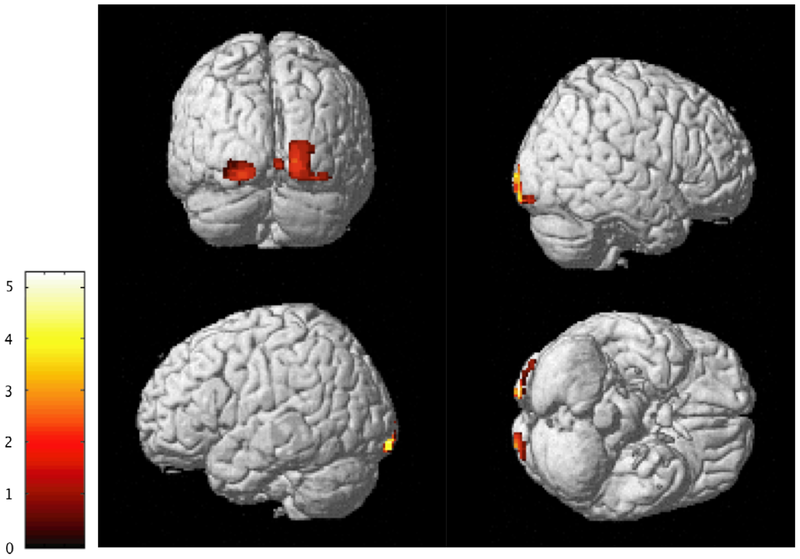

The researchers gave each of the 176 participants a questionnaire to assess their levels of empathy. Then the researchers imaged their brains using voxel-based morphometry, a neuroimaging technique that uses statistics to compare concentrations of gray matter in specific parts of the brain.

The people who had higher levels of affective empathy on the questionnaire had more gray matter concentrated near the insula, a prune-sized part of the brain that generates our strongest emotions, enables us to react emotionally to music or art, and reads body states like hunger. Those who scored higher in cognitive empathy on the test had greater gray matter density in the midcingulate cortex, a part of the brain connecting the two hemispheres that processes social information and helps with decision-making. These results indicate that the two different types of empathy result from different neurological constructs, the study reads.